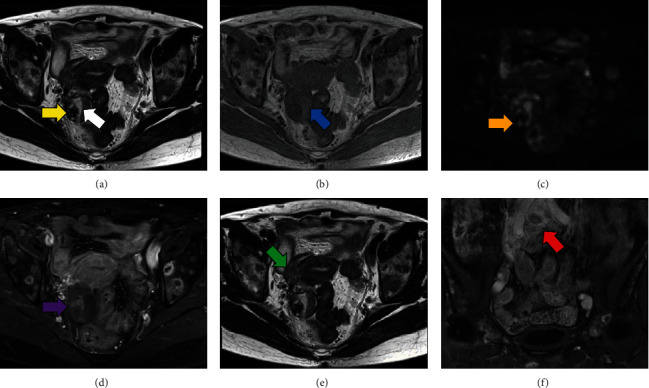

诊断性腹腔镜检查在治疗妇科癌症方面非常有用,但偶尔也会发现其他恶性肿瘤。隐匿性乳腺癌(OBC)是指没有公认的原发性乳腺病变的转移性乳腺癌。我们报告了一例罕见的通过腹腔镜发现的隐匿性乳腺癌。一名 64 岁的女性因背部疼痛来我院就诊。磁共振成像(MRI)显示右侧卵巢有一个 50 毫米的多囊性肿瘤,内部有一个结节。正电子发射断层扫描/计算机断层扫描显示多个淋巴结有异常积聚,卵巢肿瘤结节有中度积聚,乳房无积聚。怀疑是卵巢癌,于是进行了腹腔镜诊断。腹腔镜下观察到右侧卵巢有一个囊性肿瘤,右侧圆韧带有一个 10 毫米的结节,并进行了部分切除。免疫组化病理结果显示,圆韧带结节的特征与乳腺癌一致,但卵巢肿瘤是血清粘液性边界肿瘤。磁共振成像显示没有乳腺病变。因此,该恶性肿瘤被诊断为卵巢癌。

Diagnostic laparoscopy is useful in the management of gynecological cancers; however, it can occasionally result in the detection of other malignancies. Occult breast cancer (OBC) is metastatic breast cancer without a recognized primary breast lesion. We report a rare case of OBC that was detected laparoscopically. A 64-year-old female presented to our hospital with back pain. Magnetic resonance imaging (MRI) revealed a 50 mm multicystic tumor with an internal nodule in the right ovary. Positron emission tomography/computed tomography showed abnormal accumulation in multiple lymph nodes, moderate accumulation in the ovarian tumor nodule, and no accumulation in the breasts. Ovarian cancer was suspected, and a diagnostic laparoscopy was performed. Laparoscopically, a cystic tumor in the right ovary and 10 mm nodule in the right round ligament were observed and partially resected. Immunohistopathologically, the nodules of the round ligament exhibited features consistent with those of breast cancer, but the ovarian tumor was a seromucinous borderline tumor. MRI revealed no breast lesions. Therefore, the malignancy was diagnosed as an OBC.